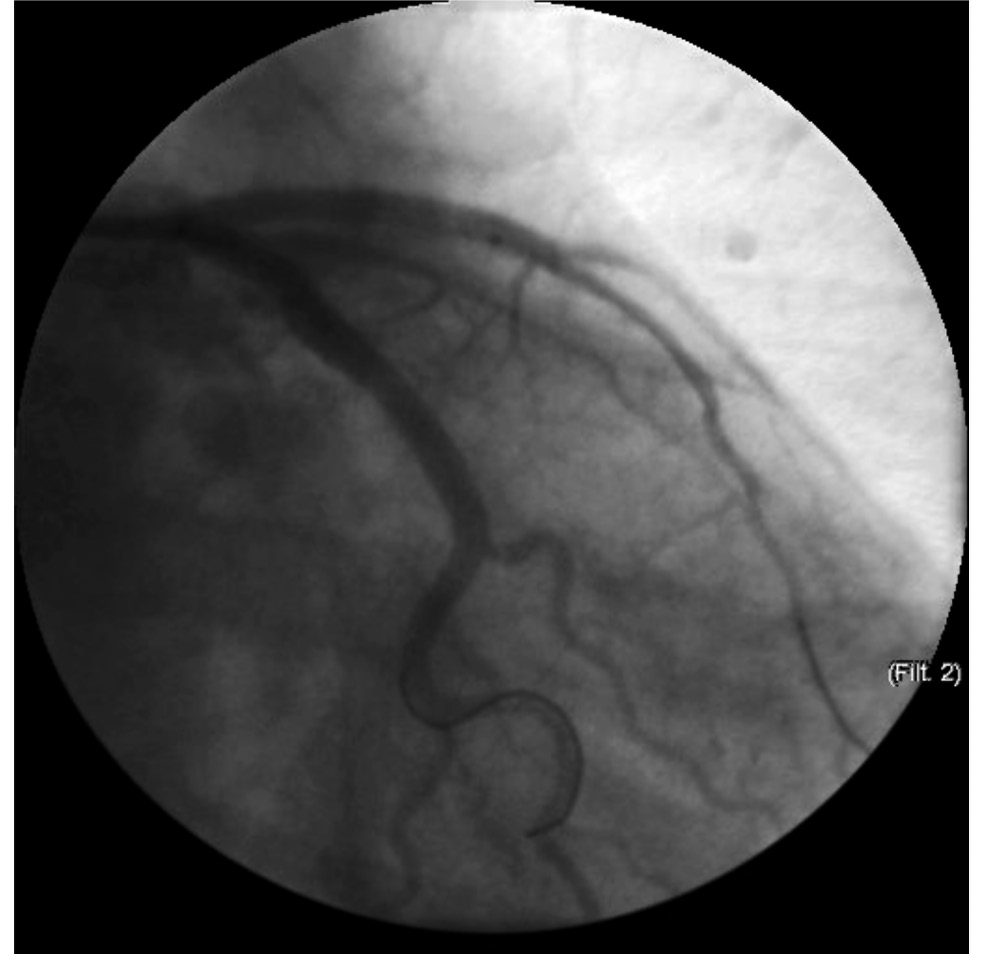

Принимая во внимание клиническую картину классической ангинозной боли, изменения на ЭКГ и вираж маркёров повреждения миокарда (тропонин Т — 778,2 пг/мл, клиническое пороговое значение — 100,0 пг/мл), пациентке была экстренно выполнена коронарография (КАГ), по результатам которой визуализировалась ангиографическая картина 95% стеноза проксимальной трети передней межжелудочковой артерии (ПМЖА) от устья с переходом на проксимальную треть со снижением кровотока до TIMI II (TIMI — шкала оценки перфузии КА после точки окклюзии при КАГ; рис. 2).

Рис. 2. Коронарограмма пациентки К. при поступлении. 95% стеноз передней межжелудочковой артерии от устья с переходом на проксимальную треть.

Fig. 2. Coronarogram on admission. Stenosis of 95% of AIVA from the orifice with transition to the proximal third.

Ствол левой КА (ЛКА), диагональная (ДВ) и огибающая ветвь (ОВ) ЛКА, правая КА и ветви правой КА — без гемодинамических значимых изменений (рис. 2, 3). Принято решение об экстренной реваскуляризации ПМЖА.